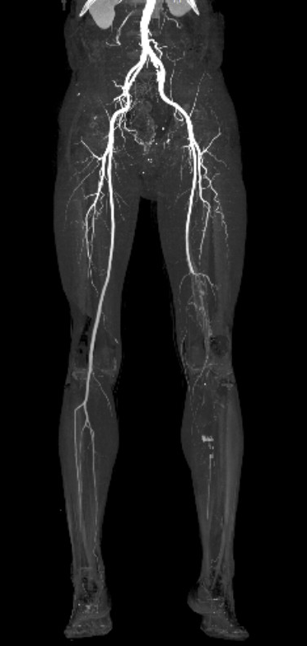

★ 病例2

51岁男性,间歇性跛行反复发作,经历多次PTA、CDT、支架植入等复杂治疗

2019.07 间歇性跛行3个月,PTA+CDT(8天)

2022.05,足趾麻木,支架植入

2023.05,间歇性跛行3个月,PTA+支架植入

治疗心得:50岁以上患者诊断困难;病灶进展迅速,治疗间隔缩短,难度增加;完全戒烟至关重要,但临床依从性差